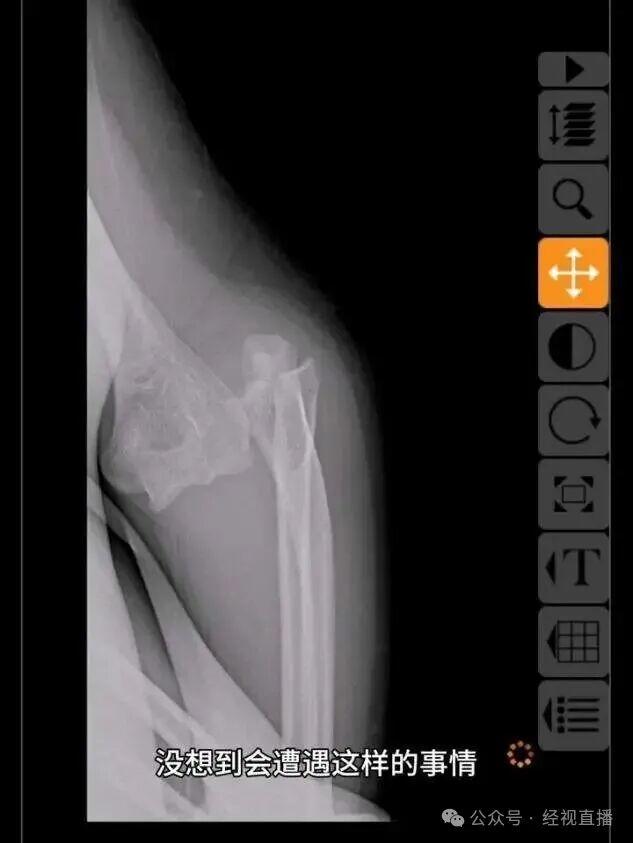

近日,一名IP属地为北京的网友发帖称,9月19日上午,其在骑行哈啰单车上班途中,车辆前轮突然抱死,致其摔伤,左手肘骨折,需手术治疗。

图/网络截图